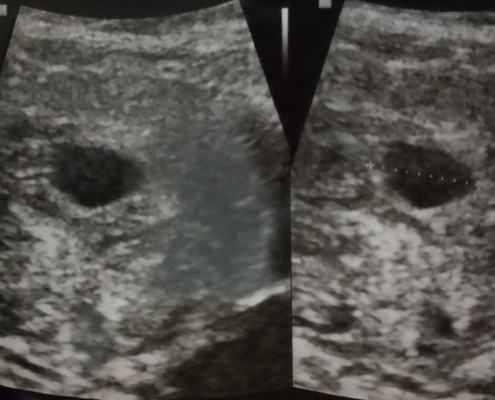

Hamil 7w 5d

Sedih yah bun...hamil 7w 5d pas usg blm ada bayinya. katong gede tp kosong. disuruh balik 2 minggu lg. kalo ga ada isi nya juga kemungkinan bs dikuret. udh di kasih vitamin n penguat kandungan sm dokter krna ada ngeflek tp dikit banget hanya nempel di tisu pas lap itu pun dikit sekali ga smpi setetes. apakah bunda pernah mengalami hal yg sama, dan gimana hasil nya? rasanya 2 minggu lagi ak ga berani balik ke dokter karna takut. hiks... saya udh konsul sm 4 dr.spog dsn hasil nya sama disuruh balik lg 2 minggu.

Memang gitu mba.. Gunanya kita wajib USG di awal kehamilan adalah untuk memastikan memang ada kantong di rahim kita. Kantong ini harus diamati, apakah kelak akan muncul embryo disitu. Dan itu berjarak 1-2 minggu. Dokter tau kapan embryo seharusnya akan terlihat di USG. Maka disarankan wajib kembali kontrol kapan. Nah biasanya setelah embyro nampak, kita dikasih penguat kandungan. Semoga mba dapet berita gembira ya 2 minggu lagi dan akan menjadi bunda ๐